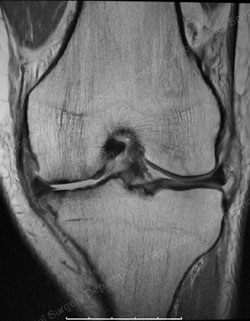

Figure: A valgus stress view shows an intact lateral compartment in a good candidate for a unicondylar knee replacement

The knee is made up of three compartments: the medial compartment (located on the inside of the knee), the lateral compartment (located on the outside of the knee), and the patellofemoral compartment (located in the front of the knee). In a particular group of osteoarthritis patients, however, the entire knee is not affected by the arthritis. In some patients, only the medial compartment (or, less commonly, only the lateral compartment) may be affected by the disease. For those patients, unicondylar (partial) knee replacement can be considered a treatment option. The term “unicondylar” refers to the replacement of only one section of the smooth bone ends (condyles) – the medial or lateral compartment – as compared to total knee replacement, which involves replacement of all three compartments.

The concept of unicondylar knee replacement entails replacement of the diseased medial or lateral compartment and preservation of the anterior (front) and posterior (rear) cruciate ligaments. In contrast, a standard, posterior stabilized total knee replacement requires the removal of both the anterior and posterior cruciate ligaments, and the implant substitutes for these ligaments.